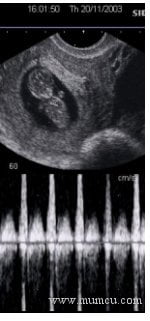

12_dop_kalpBunlar dışında renkli doppler incelemesi erken dönemde bebeğin kalp atımlarının görülmesi ve dinlenmesi amacıyla da kullanılır. Yandaki fotoğrafta 9 hafta 6 günlük bir gebelikte bebek kalp atımlarının doppler ile incelenmesi izenmektedir.Başka bir uygulama alanı da bebeğin kalbinden çıkan ana damarların gözlenmesidir. Rutin gebelik ultrasonografisi sırasında bebeğin idrar kesesinin iki yanında damarsal yapıların gözlenmesi de olası bir anomali riskini azaltan bir bulgudur.